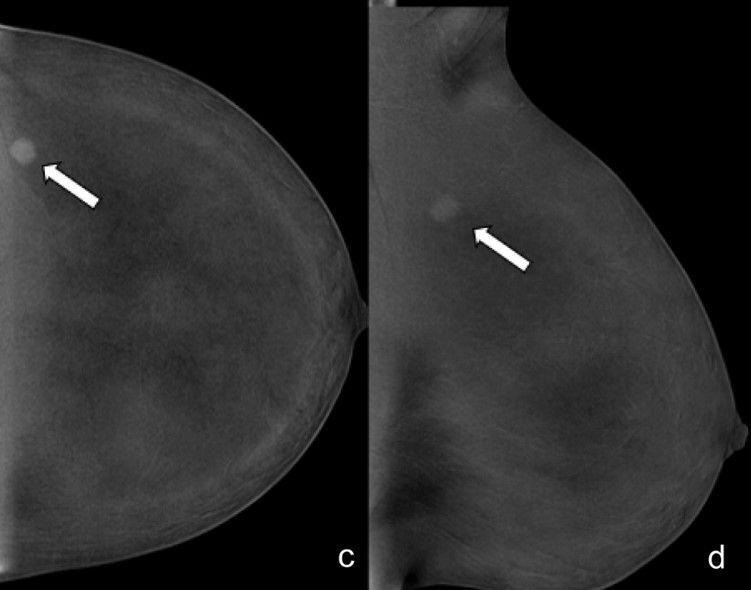

Misdiagnosis in breast imaging can delay treatment, cause unnecessary procedures, and erode patient trust, leading to worse prognosis and raise healthcare costs.

How do we address this? Accurate imaging, continuous education, and clear communication among providers are key to minimizing risks and improving patient care. (Isabelle Thomassin-Naggara et al.)

πŸ”— buff.ly/4fHjHHw

A study on inter-reader agreement of the breast imaging reporting and data system (BI-RADS) contrast-enhanced (CEM) lexicon found moderate to substantial agreement for most features, with lower agreement for non-mass enhancement and enhancing asymmetry. (Calogero Zarcaro et al.)

πŸ”— buff.ly/3OqsjpP